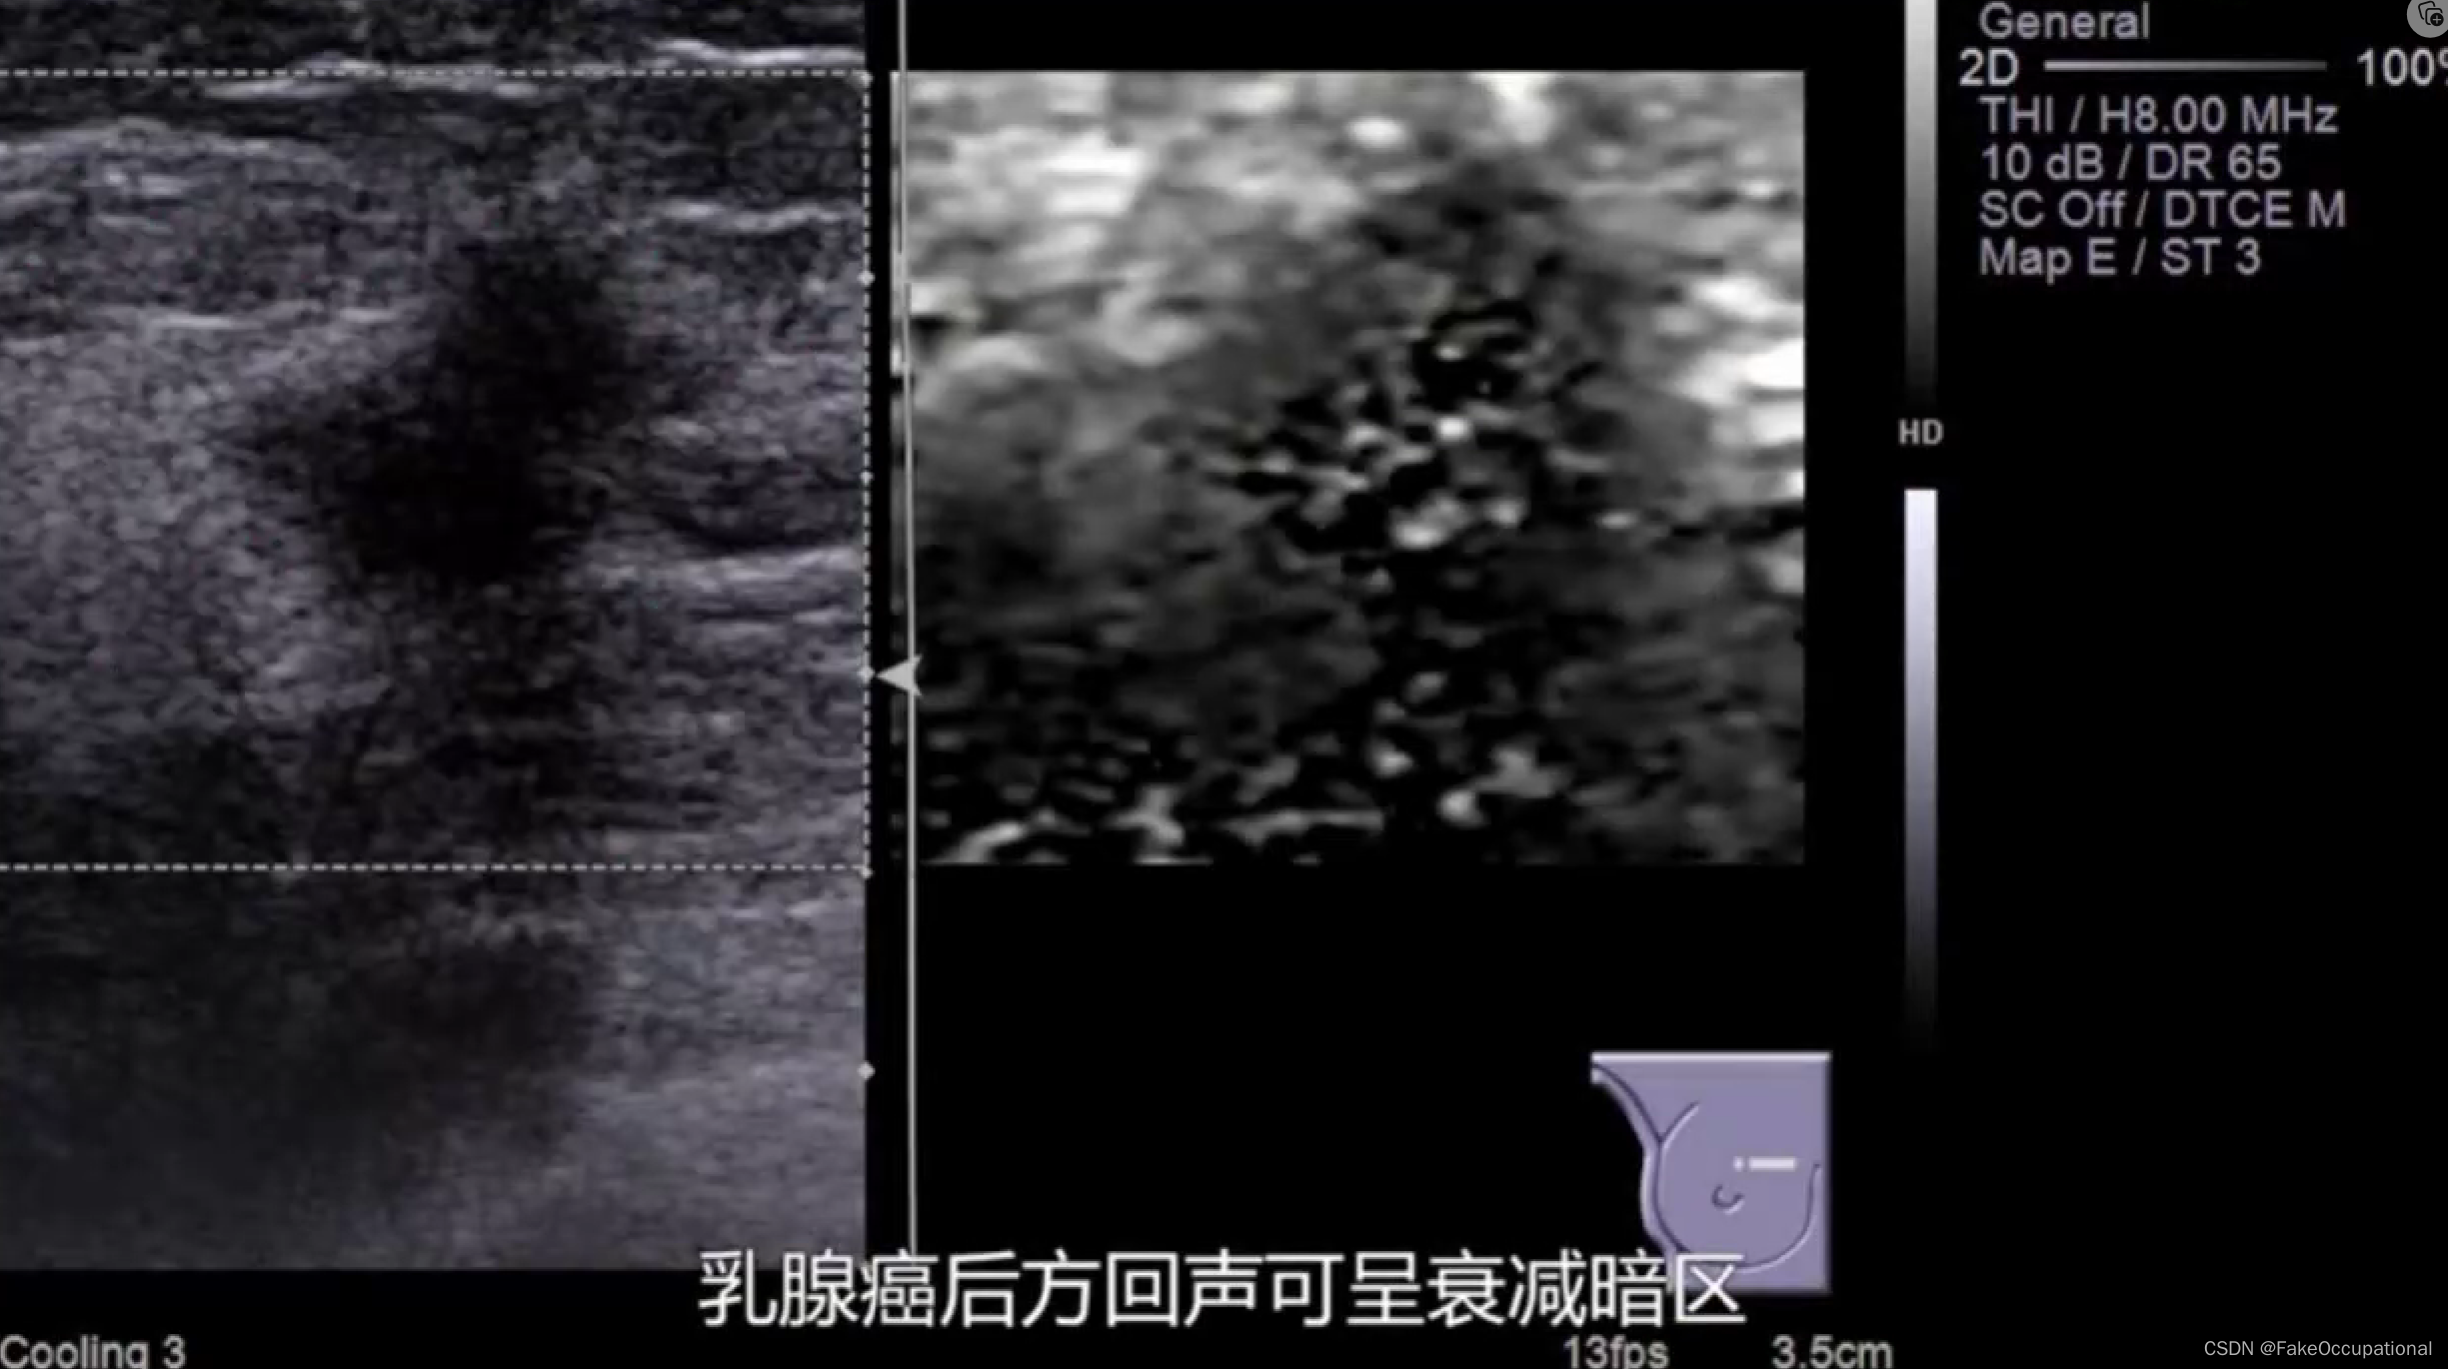

乳腺癌

- 其理论依据是恶性肿瘤常星离心性生长